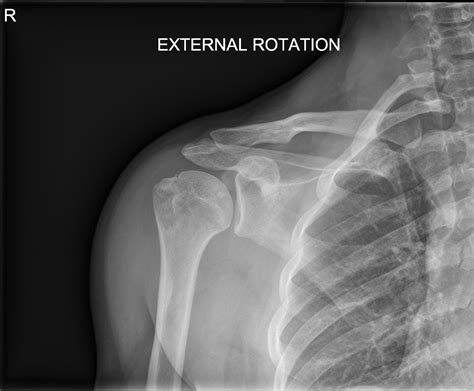

Diagnostic Imaging and Rehabilitation

Diagnosing issues involving the greater tubercle of humerus typically involves a combination of physical examinations and imaging techniques. X-rays are the gold standard for identifying bony fractures, while MRI scans are essential for visualizing the soft tissues—specifically the rotator cuff tendons—that attach to the bone. Physicians look for irregularities in the bone surface, bone spurs (osteophytes), or evidence of tendon tearing near the insertion sites.